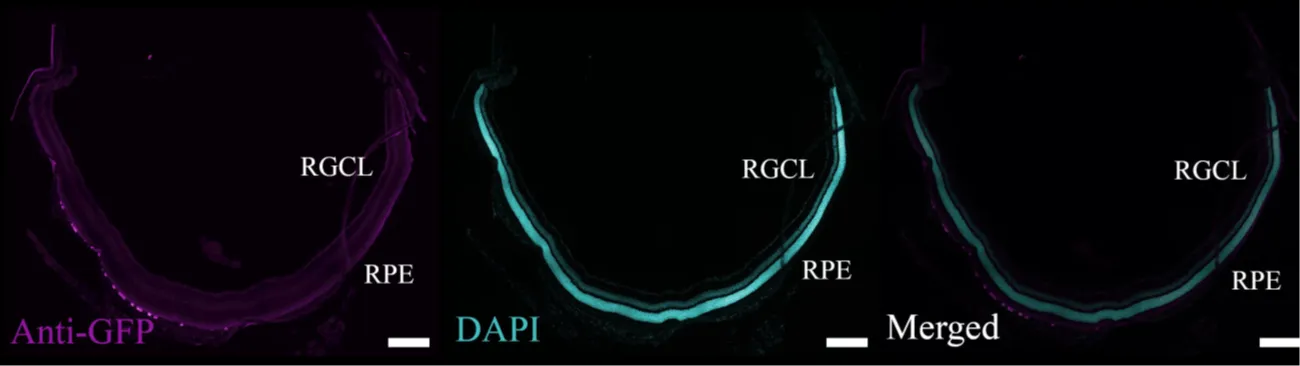

As part of the tissue and molecular analysis, we offer routine or custom histology and immunohistochemistry services as well as gene expression, vector biodistribution, and protein quantification assessed through qPCR, Western blot, and ELISA, giving sponsors detailed insight into the performance and safety of their gene therapy drug candidate.

Representative images of retinal cross-sections immunostained against GFP (magenta) and counterstained with DAPI (cyan)